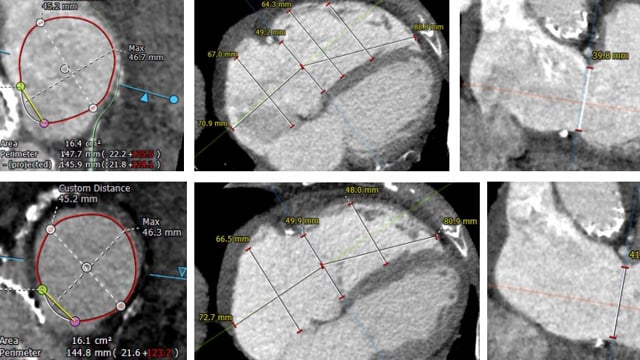

Innovations In Transcatheter Tricuspid Valve Intervention

Innovations in transcatheter tricuspid valve intervention www.pcronline.com

tricuspid valve transcatheter innovations intervention resources